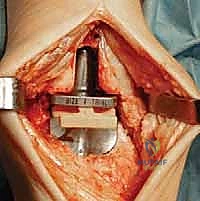

3. إزالة الأسطح التالفة (تحضير العظام)

باستخدام أدوات جراحية دقيقة وموجهات خاصة، يتم إزالة الغضاريف التالفة وجزء رقيق جداً من العظام المريضة من نهايتي عظمة الظنبوب وعظمة الكاحل (Talus). يتم تشكيل العظام بدقة لتتطابق تماماً مع شكل أجزاء المفصل الصناعي.

4. تركيب المفصل الصناعي (Implantation)

يتكون مفصل الكاحل الصناعي الحديث عادة من ثلاثة أجزاء:

* قطعة معدنية علوية: تُثبت في عظمة الظنبوب (الساق).

* قطعة معدنية سفلية: تُثبت في عظمة الكاحل.

* قطعة بلاستيكية (بولي إيثيلين عالي الكثافة): توضع بين القطعتين المعدنيتين لتنزلق بسلاسة وتمتص الصدمات، محاكيةً وظيفة الغضروف الطبيعي.

يتم تثبيت هذه الأجزاء بإحكام (إما عن طريق الضغط المباشر لتشجيع نمو العظم حولها، أو باستخدام أسمنت طبي خاص).